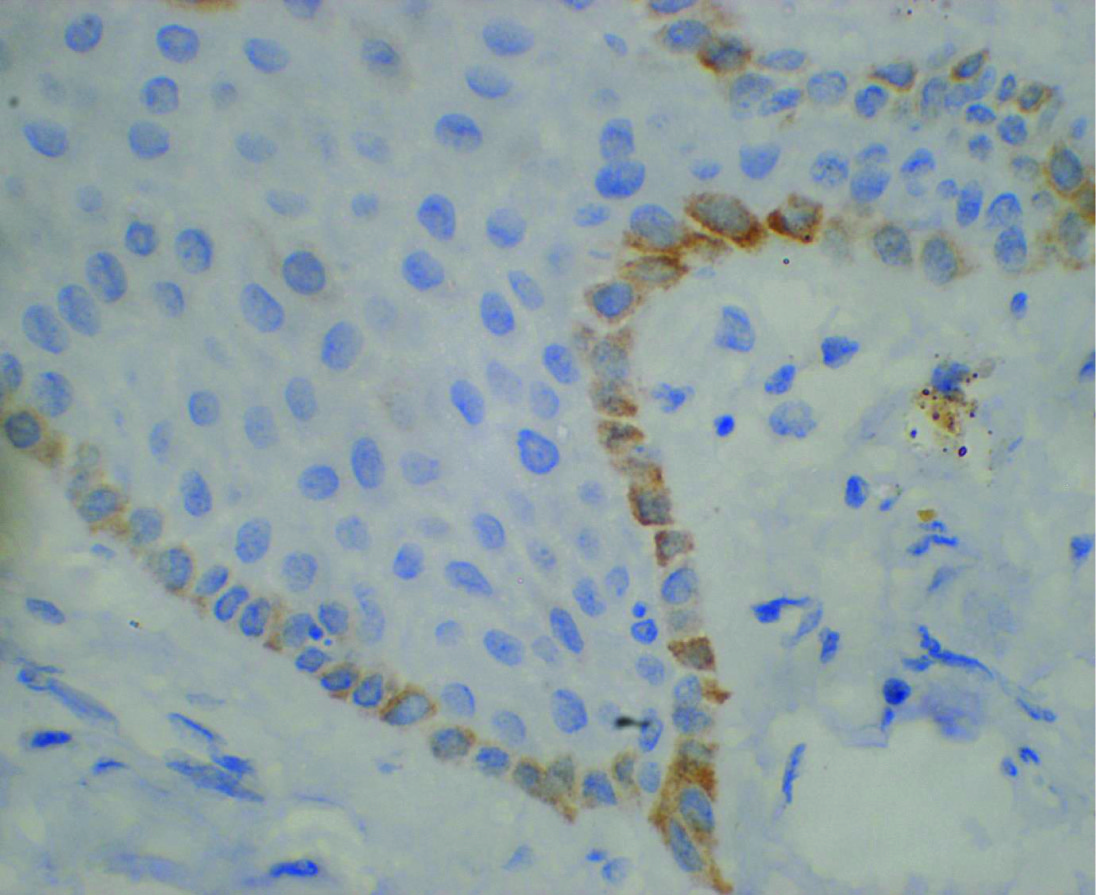

Ck-19 staining in the basal cells of NRM - 40x

Diffuse positivity of NSE in NRM

Faint positivity to synaptophysin in NRM 20X

Faint CD99 staining in the basal cells of NRM - 20X

Based on the criteria followed for assessing the expression in the normal mucosa, it was seen that a positive staining was obtained in all the 10 cases for NSE [Table/Fig-8], in eight cases for Synaptophysin [Table/Fig-9] and in six cases for CD99 [Table/Fig-10]. The staining was stronger,diffuse and extended to the superficial layers in case of NSE, and was specifically restricted to the basal layers in case of CD99 [Table/Fig-10].